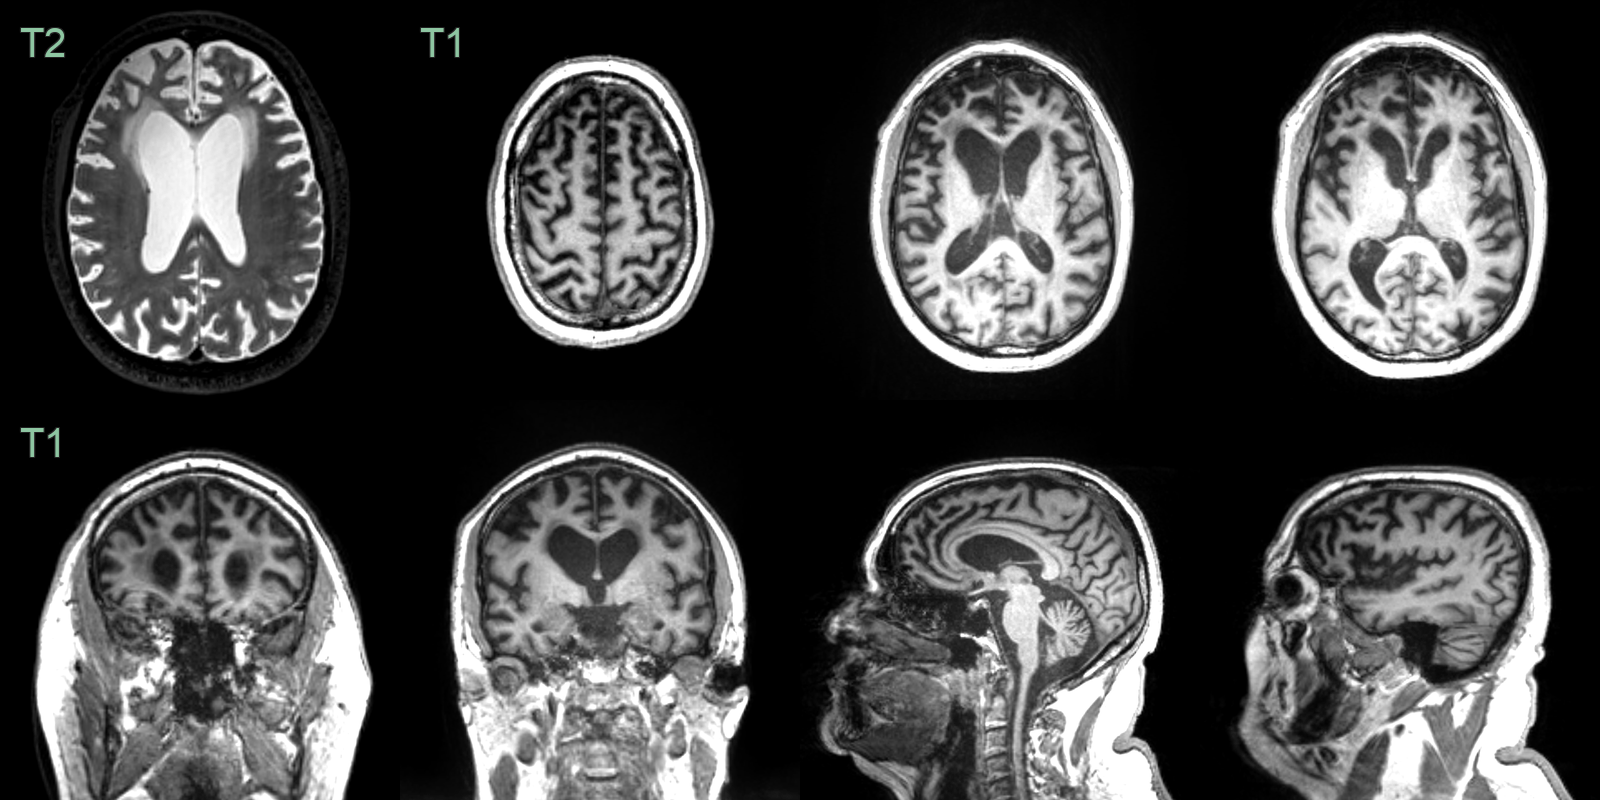

- A 60-year-old patient presented with apathy and increased weight. The patient's partner reported episodes of reckless spending in the preceeding year. The patient had a strong family history for dementia.

- MRI showed symmetrical frontal lobe atrophy. The frontal horns were larger than the trigones. The olfactory sulci were wided ("Crab sign").

- Genetic testing revealed a C9ORF72 mutation as the cause of the frontotemporal dementia.